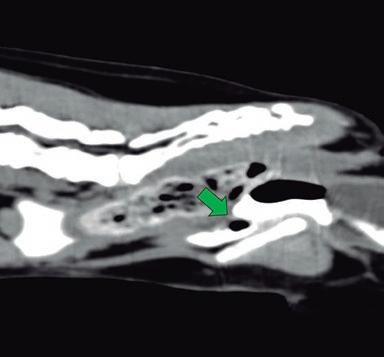

Agujas de acceso vascular